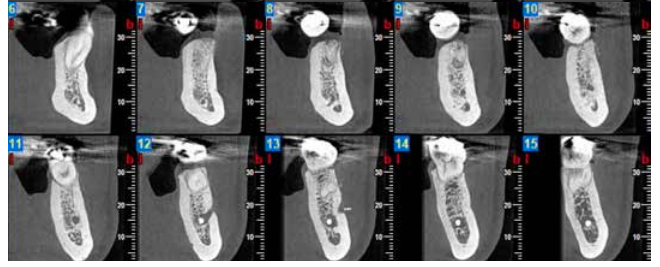

Materials and methods: A study was carried out on 6 patients from the Faculty of Dentistry of the Complutense University of Madrid performing the technique of alveolar ridge preservation. Two groups were established, a test group in which the alveolar socket was filled with calcium phosphate and added silicon and a control group where the socket was filled with bovine hydroxyapatite. After 3 months, a cone-beam computed tomography was performed to evaluate the bone density achieved by both biomaterials.

Results: The average bone density achieved in the group treated with calcium phosphate and added silicon was 1100,40 ± 111,19 Hounsfield units whereas in the group treated with bovine hydroxyapatite the average bone density was 1029,46 ± 95,16 Hounsfield units.

Conclusions: Both biomaterials seem to present a similar behaviour in terms of densitometric results obtaining a density greater than 1000 Hounsfield units, having the calcium phosphate and added silicon the highest density.

The aim of this study was to evaluate the bone density, measured in Hounsfield units (HU), achieved by a new biomaterial, composed of calcium phosphate with added silicon (CAPO-Si), and to compare it with bovine hydroxyapatite (HAB) in the PAP technique.